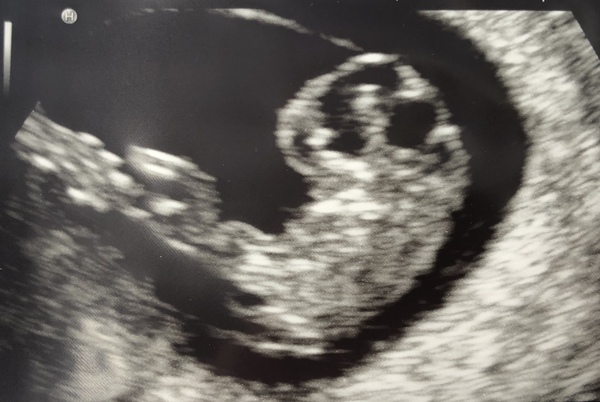

@strawberrye that's a lovely clear picture. Congratulations!

@catconfusion thanks! Great news on your scan too, it's so amazing to see them wiggling their little arms when they are so tiny isn't it?

@Catconfusion lovely scan pic, glad all is well!

Hi ladies, joining the roll call. Lovely to see so many scan pics.